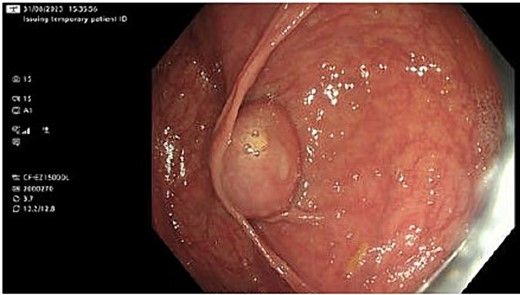

She had a colonoscopy 2 weeks later. This showed a mass at the appendiceal orifice similar to a mucocele as shown in Fig. 1 from which biopsies were taken. Four polyps were also removed from the right colon, the largest being an 18 mm lesion in the ascending colon.

Histology showed normal colonic mucosa for the biopsies from the suspected mucocele, while the polyps were low grade tubular adenomas with one tubulovillous adenoma with low grade dysplasia.